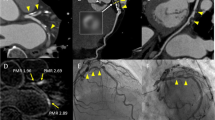

Because our previous study had demonstrated that a 2D-PMR cutoff value of 1.4 is a significant predictor of coronary events [5], we subdivided the study patients into the following 4 groups according to the 3Di-PMR cutoff value of 51 PMR*mm3 and the 2D-PMR cutoff value of 1.4: 2D-PMR < 1.4 + 3Di-PMR < 51 PMR*mm3 (2Dlow3Dlow group: n = 78), 2D-PMR ≥ 1.4 + 3Di-PMR < 51 PMR*mm3 (2Dhigh3Dlow group: n = 6), 2D-PMR < 1.4 + 3Di-PMR ≥ 51 PMR*mm3 (2Dlow3Dhigh group: n = 15), and 2D-PMR ≥ 1.4 + 3Di-PMR ≥ 51 PMR*mm3 (2Dhigh3Dhigh group: n = 42). Figure 4 shows representative 2D and 3D plaque assessments on T1w imaging. Coronary plaques with 2D-PMR < 1.4 + 3Di-PMR ≥ 51 PMR*mm3 in the proximal right coronary artery (a patient with 2Dlow3Dhigh plaque; Patient A: panels a–e), 2D-PMR ≥ 1.4 + 3Di-PMR < 51 PMR*mm3 in the proximal left anterior descending artery (a patient with 2Dhigh3Dlow plaque; Patient B: panels f–j), and 2D-PMR ≥ 1.4 + 3Di-PMR ≥ 51 PMR*mm3 in the proximal left anterior descending artery (a patient with 2Dhigh3Dhigh plaque; Patient C: panels k–o) and corresponding CTA images are shown. Coronary CTA (a, f, k), and axial images (b, g, l), sagittal images (c, h, m), color maps (d, I, n), and volume images (3D plaque: e, j, n) and non-contrast T1w images are shown in Figure 4. Among the four groups based on 2D-PMR and 3Di-PMR cutoff values, the incidence of pMI was highest in the 2Dhigh3Dhigh group (64.3%), and lowest in the 2Dhigh3Dlow group (0%) (P < 0.001, Figure 5). Of note, even in patients with 2D-PMR < 1.4, the incidence of pMI among those with 3Di-PMR ≥ 51 PMR*mm3 was significantly higher than in patients with 3Di-PMR < 51 PMR*mm3 (2Dlow3Dhigh group: 46.7% vs. 2Dlow3Dlow group: 15.4%, P = 0.006; Figure 5).

Representative 2-dimensional and 3-dimensional plaque assessment on T1-weighted imaging. Coronary plaques with 2Dlow3Dhigh in the proximal right coronary artery (2D-PMR, 1.14; 3Di-PMR, 237 PMR*mm3; Patient A: a–e), 2Dhigh3Dlow in the proximal left anterior descending artery (LAD) (2D-PMR, 1.50; 3Di-PMR, 43 PMR*mm3; Patient B: f–j), and 2Dhigh3Dhigh in the proximal LAD (2D-PMR, 1.96; 3Di-PMR, 344 PMR*mm3; Patient C: k–o). Computed tomography angiography (CTA) images (a, f, k), and axial images (b, g, l), sagittal images (c, h, m), color maps (d, I, n), and 3D region of interests (3D plaque: e, j, n) on T1w images are shown. Yellow circles indicate percutaneous coronary intervention target lesion sites on CTA. Yellow arrows indicate lesions on T1w imaging corresponding to a lesion on angiography that underwent intervention.